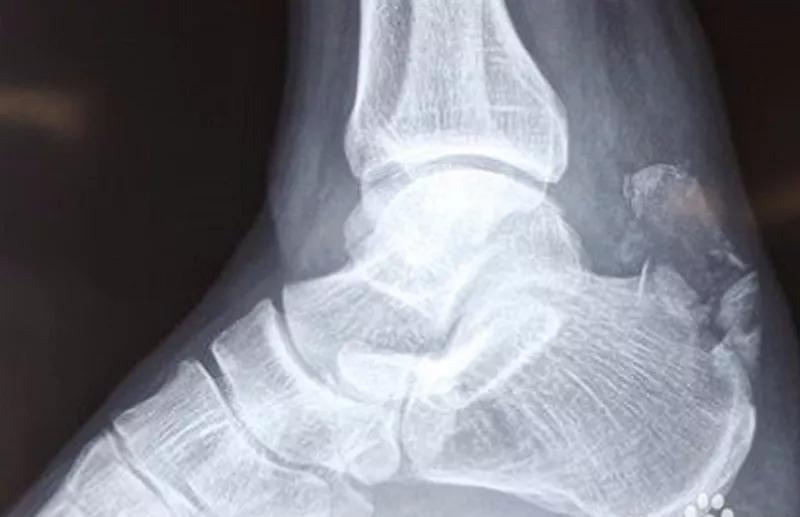

X线:了解跟腱有无钙化,止点撕脱骨折等。